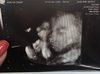

Fanka BB :)